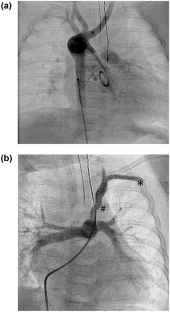

Fig. 1

Supplementary file2 Online Resource Video 1: Aortography showed right aortic arch, late filling of isolated left subclavian artery and pulmonary artery through PDA (MPG 5046 KB)

Supplementary file3 Online Resource Video 2: Right subclavian artery angiogram showed numerous small connections from the right vertebral artery through head and neck vessels to LVA to supply the ILSA with significant flow into the pulmonary arteries (MPG 3938 KB)

Supplementary file4 Online Resource Video 3: ILSA angiogram showed it is connected to the pulmonary artery through a left PDA (MPG 3936 KB)